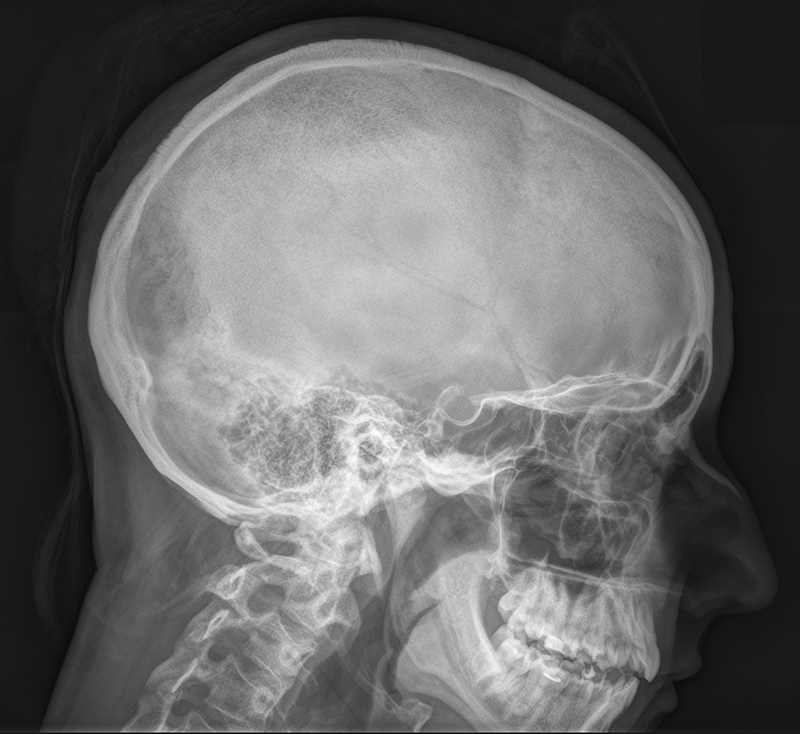

Рентгенография турецкого седла (со снимком)

Рентгенография турецкого седла используется для подтверждения диагноза при различных заболеваниях гипофиза, сопровождающихся частыми головными болями, нарушением роста (карликовость или гигантизм), выраженными нарушениями менструального цикла у женщин и бесплодием.

Исследование проводится в положении стоя боком.